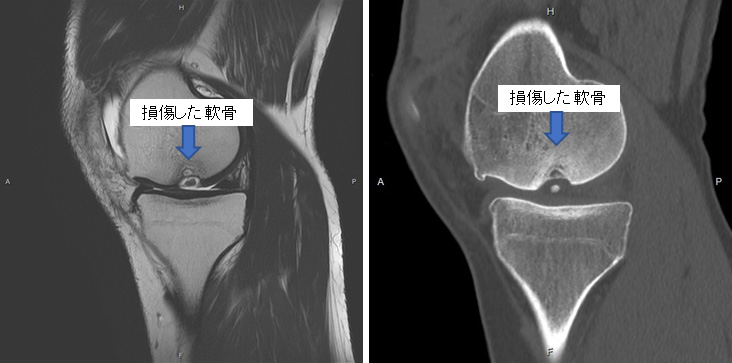

【図1 :MRI・CTでみえる離断性骨軟骨炎(左:MRI、右:CT)】

離断性骨軟骨炎は成長期に生じやすく、軟骨が骨ごと剥がれてしまう障害です。またこの他に軟骨損傷の病態は様々で、離断性骨軟骨炎の他に、靭帯損傷に伴う損傷、膝蓋骨と言われる膝のお皿の脱臼に伴う損傷、外傷やスポーツ活動などでの過度な負荷により生じる損傷などもあります。

診断には、症状の経過や診察時の医師による徒手検査などによる他の疾患との鑑別、また画像としてMRIやCTなどが用いられます(図1)。